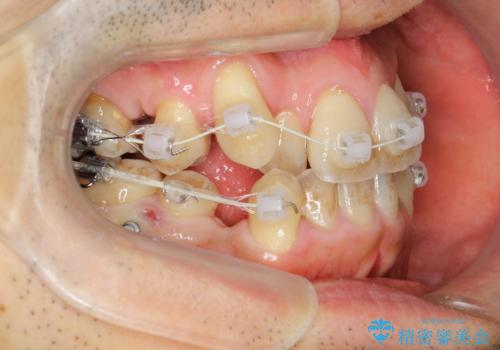

途中までは下顎は全体にワイヤーをはらずに、セクショナルワイヤーにて治療を進めています。

上顎は最初から全体にワイヤーをはっていましたが、上顎前歯部の歯肉退縮のリスクが高そうだったために、途中まで下顎と同じくセクショナルワイヤーで進めています。

八重歯(3番)などは歯肉移植も検討できればよいかなと思います。